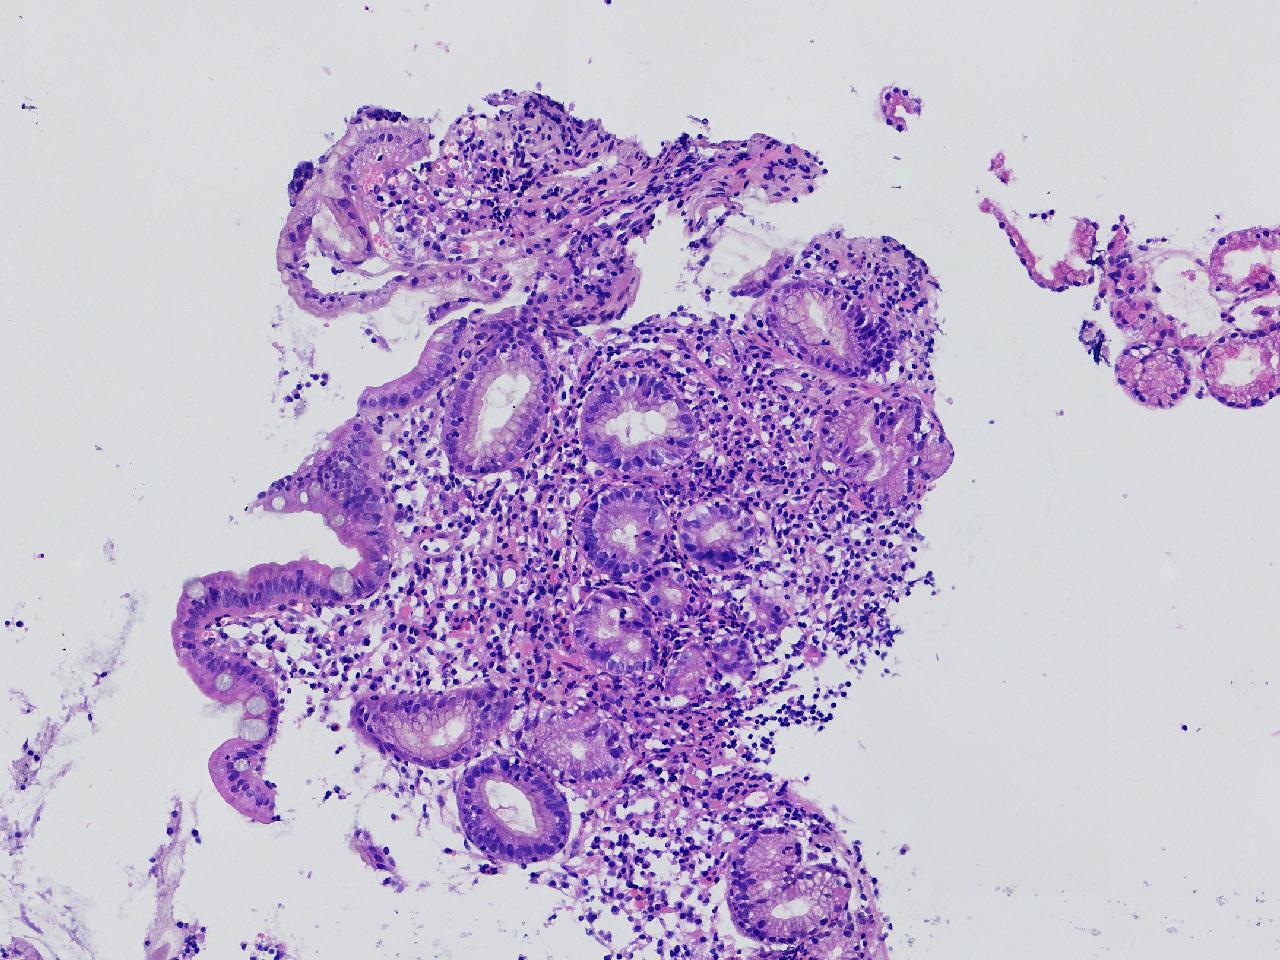

1.间质内淋巴组织有问题吗? 2.有没有低瘤变?

一般病史男,65岁,胃镜活检,胃窦粘膜红白相间,花斑样改变,大弯侧粘膜变薄,血管透见,可见多发片状充血糜烂灶及点状褐色物覆着,活检2块送检,质软弹性可。

标本名称胃窦活检

大体所见灰白色不整形软组织2块,直径均0.2厘米。

慢性萎缩性胃炎伴肠化,固有层淋巴细胞聚集

萎缩性炎,伴有肠化,淋巴组织挤压变形,感觉没有太大的问题。

炎性,无瘤变。